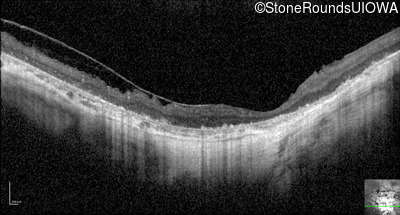

Optical Coherence Tomography - Right - Hand Motion

Exemplar / OCT Stack

OCT Stack

Optical Coherence Tomography - Left - Hand Motion